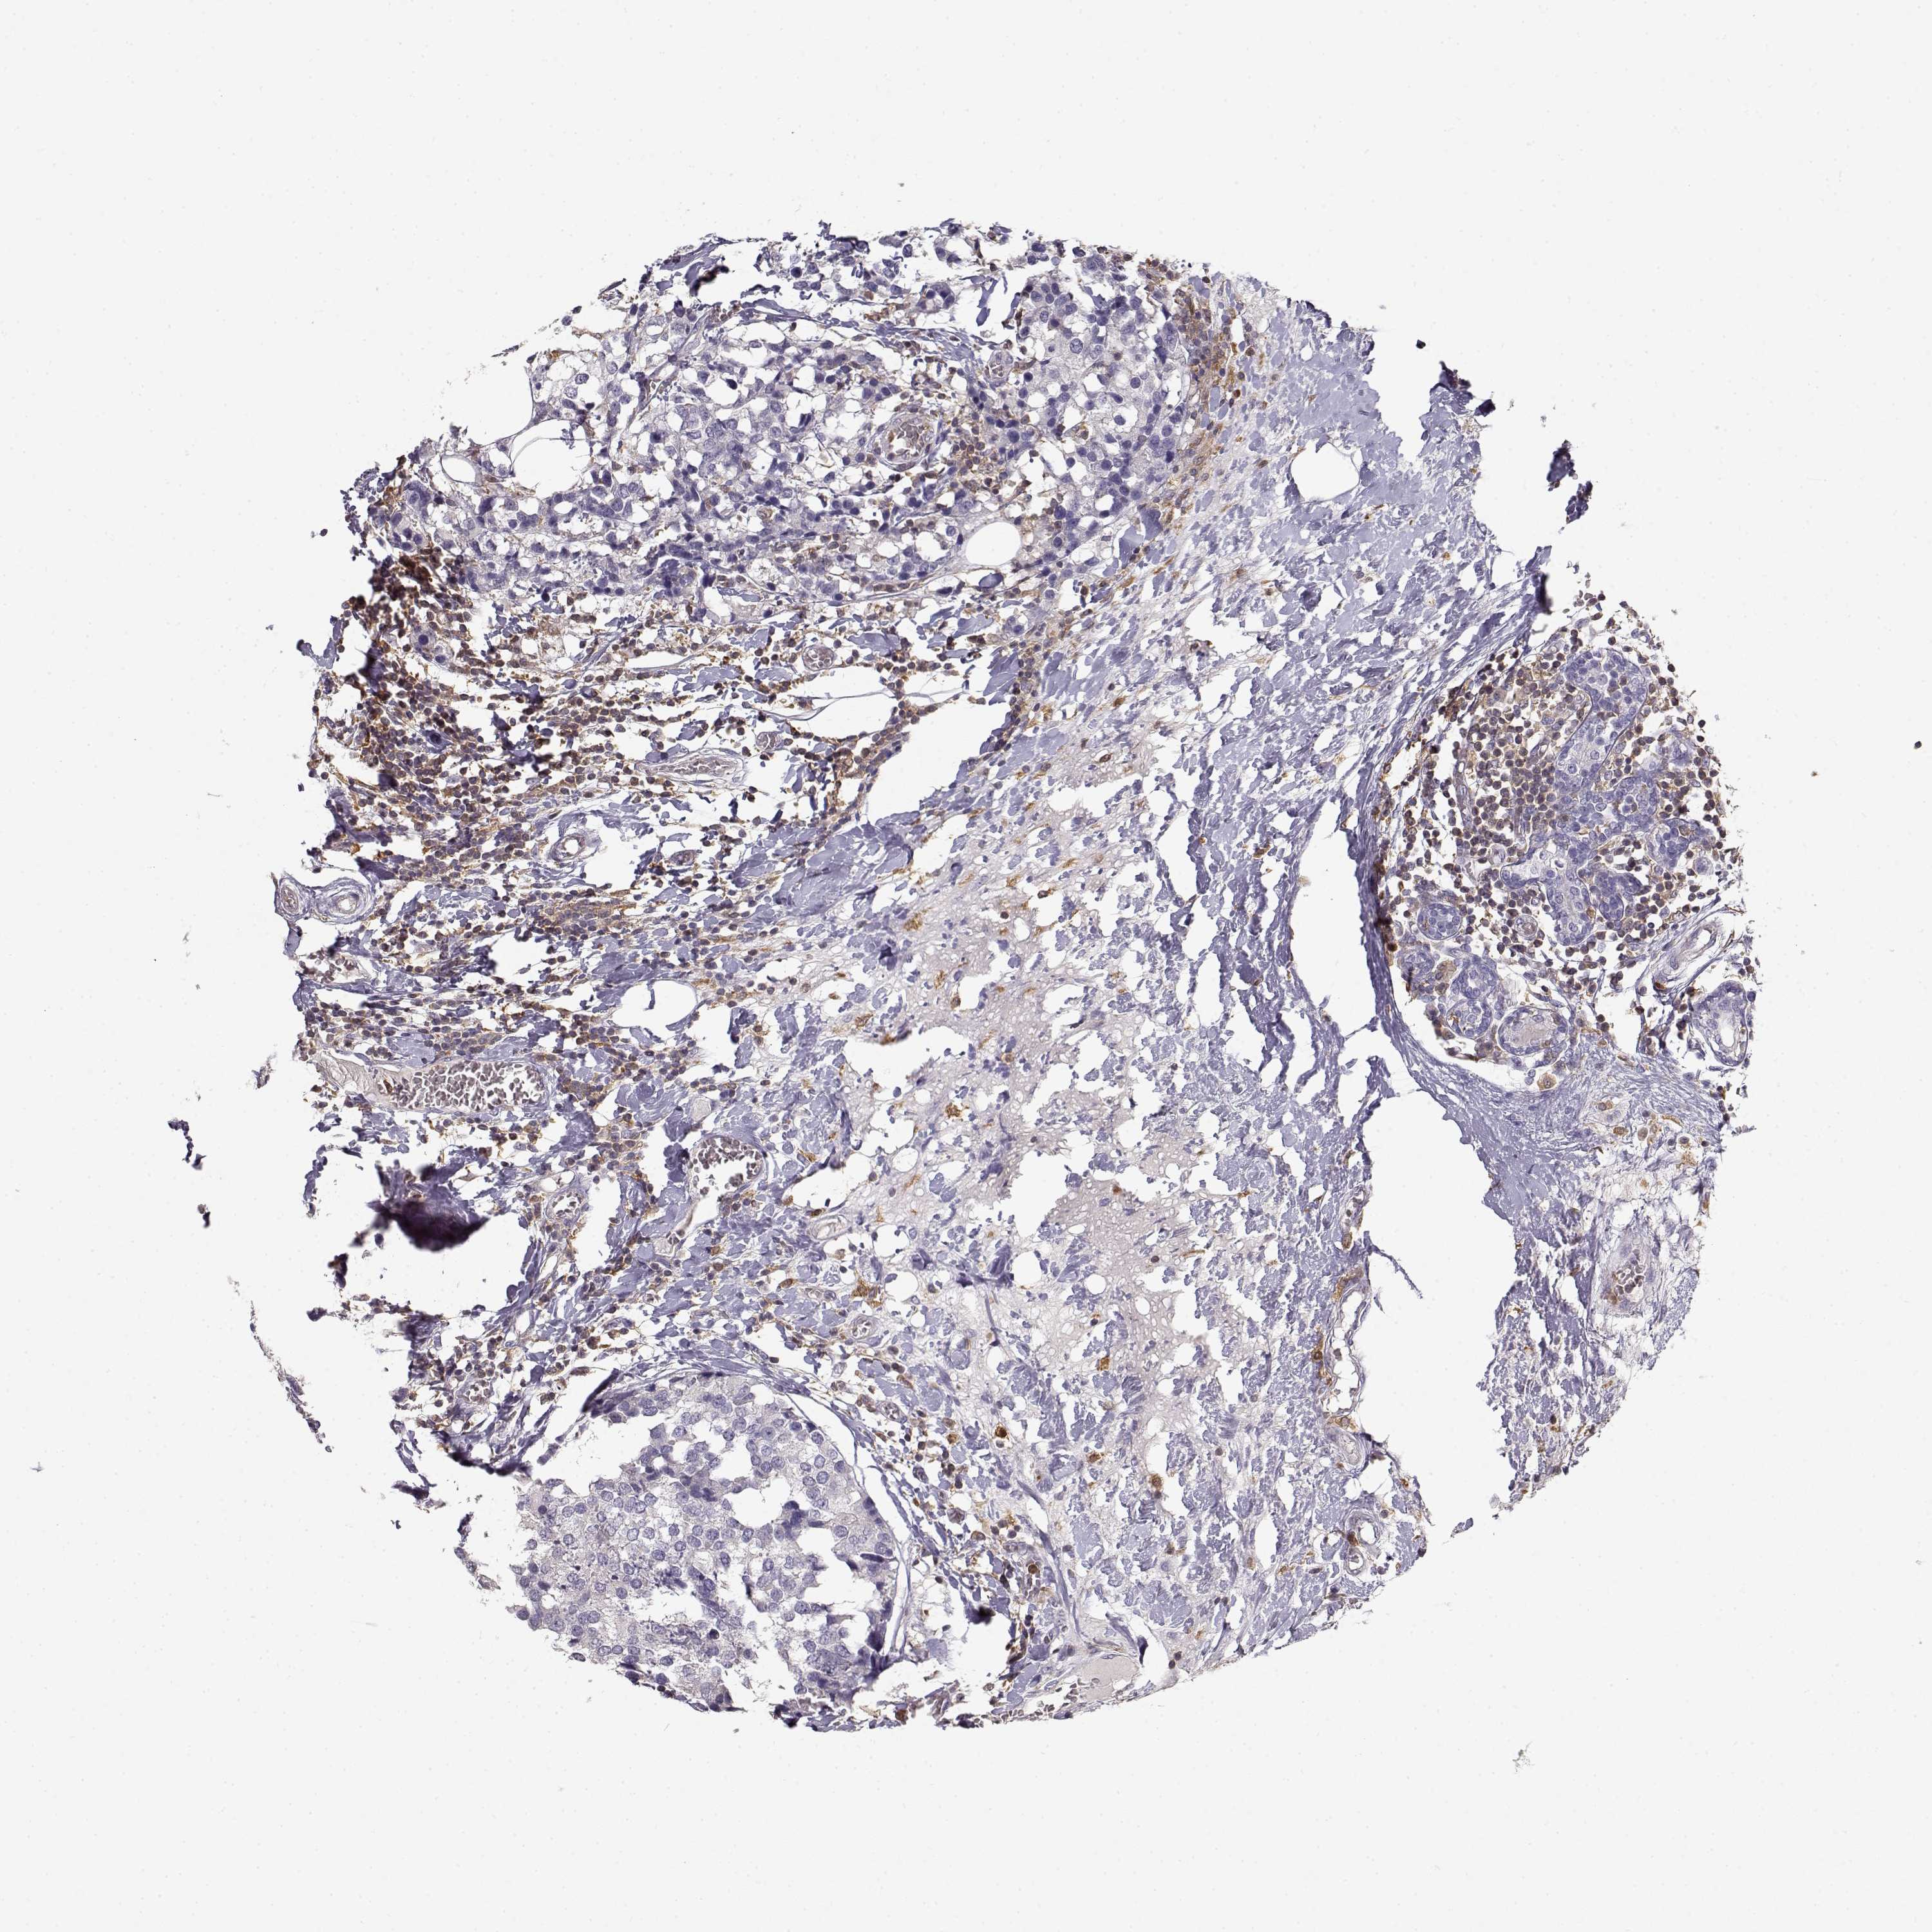

CANCER BREAST CANCER Show tissue menu

BRCA TCGA BRCA VALIDATION PROTEIN EXPRESSION